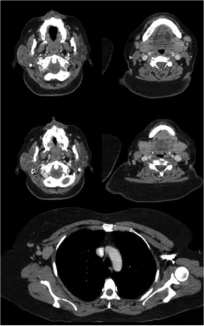

En el 2010 la paciente tuvo un aumento de volumen en el párpado superior de forma bilateral, adenopatías cervicales indoloras, además de que refirió datos de sequedad ocular y oral. El servicio de Oftalmología realizó tomografía computarizada (TC) de órbitas en la cual se apreció aumento de volumen y lesiones sólidas en fosas lacrimales bilaterales. En la TC de cuello-tórax-abdomen se observó crecimiento parotídeo derecho con densidad heterogénea y adenopatías cervicales bilaterales (figura 1), infraclaviculares, mediastinales, en cadena mamaria interna y retroperitoneales. Se realizó biopsia de párpado superior izquierdo con reporte de linfoma no Hodgkin de bajo grado, con inmunohistoquímica positiva para CD20 en forma difusa, 100% de células, negativo para proteína S-100, kappa, lambda y citoqueratinas.

Crecimientos ganglionares (7 y 10 mm) bilaterales en cuello.

Crecimientos ganglionares axilares bilaterales (32 x 20 mm)